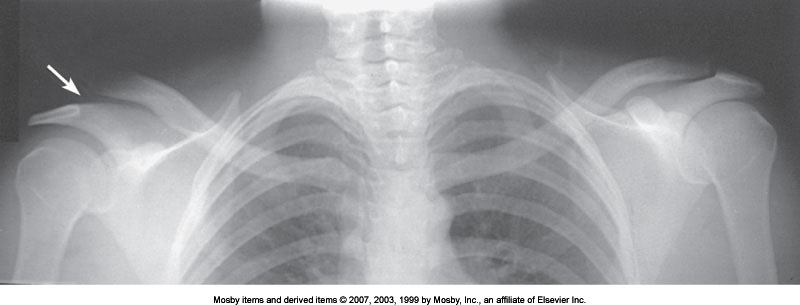

What articulation is demonstrated

AC Joint